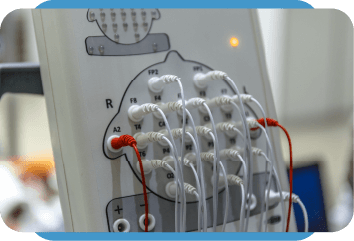

Tecnologia avançada para um diagnóstico mais preciso